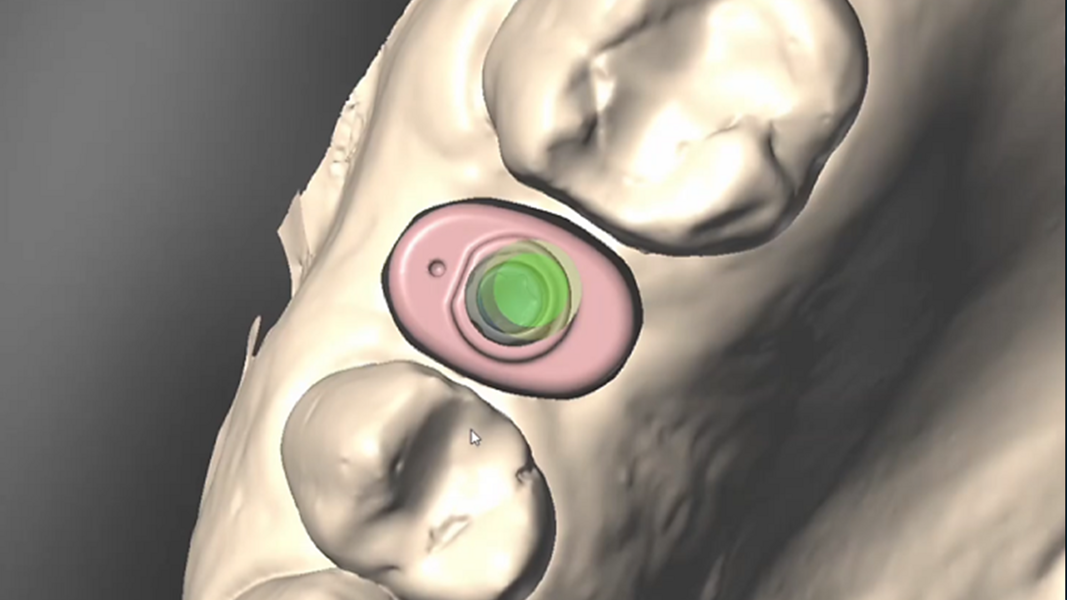

The patient’s maxillary and mandibular arches were scanned using the Straumann SIRIOS system. The scans, along with the DICOM files from the CBCT scan, were sent via Straumann AXS to Smile in a Box (Straumann) for treatment planning, surgical guide design and 3D printing of the model and surgical guides (Figs. 4, 5a–f & Figs. 6a–d).

After evaluation and validation of the plan, it was decided for site #15—where a residual root was present and the bone density was generally soft—that a Straumann BLX (Roxolid, SLActive, regular base) 4.5 × 8.0 mm implant would be placed, along with an M shape Straumann Anatomic Healing Abutment XC (regular base/wide base; gingival height: 1.5 mm). For site #25, extraction of the remaining root was planned and would be followed by the placement of a Straumann BLC (Roxolid, SLActive, regular base) 3.75 × 8.00 mm implant. This narrower site had a visible lamina dura, favourable for achieving primary stability. An M shape Straumann Anatomic Healing Abutment XC (regular base/wide base; gingival height: 1.5 mm) was also selected for this site to support proper soft-tissue emergence during the 60- to 90-day healing period. Owing to the expected post-extraction gaps between the implants and buccal bone walls, cerabone plus (botiss biomaterials) was planned to be used for grafting.

The surgical guide was inserted and verified for accurate fit. Osteotomy preparation was carried out according to the protocol generated by coDiagnostiX (Dental Wings), tailored to the planned implant types on each side (Figs. 8a–g). The Straumann BLX implant was placed into site #15, achieving primary stability at 30 N cm. The Straumann BLC implant was inserted into site #25, reaching primary stability at 50 N cm (Figs. 9a–g).